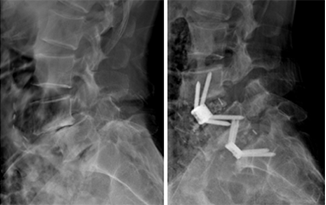

요통, 경추통, 방사통, 척추 골절, 척추 디스크, 척추관협착증, 척추전방전위증,신경차단술, 척추신경성형술, 내시경하 수핵제거술, 척추고정유합술 등

윤성훈 과장신경외과

요통, 경추통, 방사통, 척추 골절, 척추 디스크, 척추관협착증, 척추전방전위증, 신경차단술, 척추신경성형술, 디스크고주파 감압술, 양방향 / 단일공 내시경하 수핵제거술, 척추 풍선복원술, 경추/요추 퇴행성질환 교정술 등